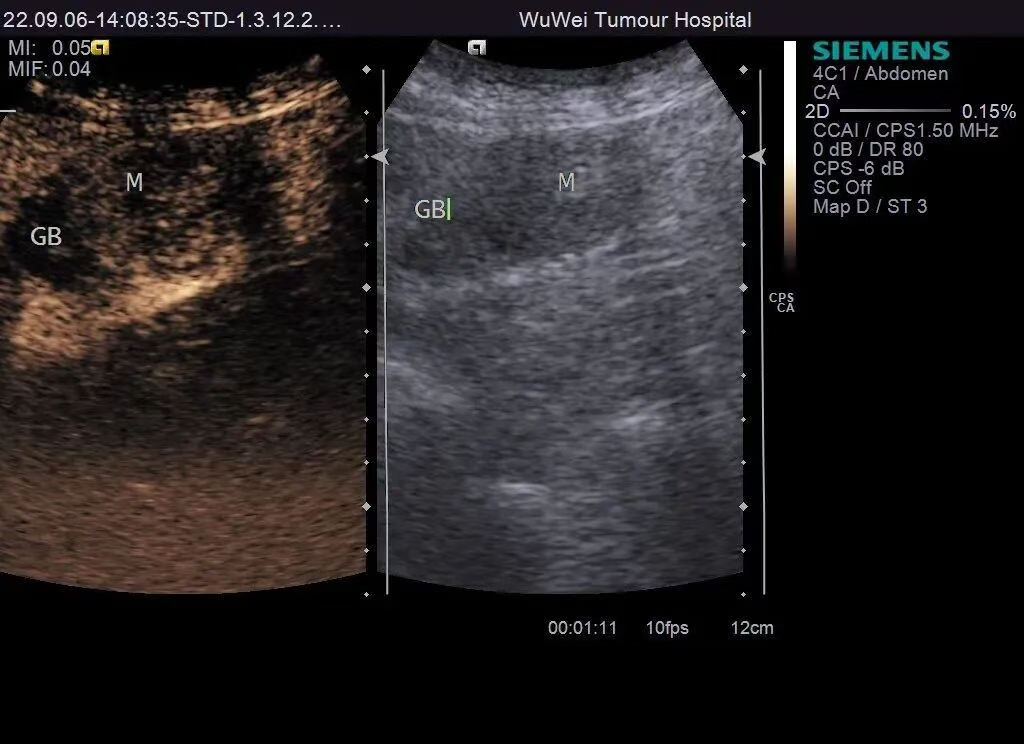

图6 超声造影灌注特征:胆囊内病灶275S消退明显,延迟期呈持续低增强

【手术病理结果】术中见胆囊约9x4cm,胆囊底部有约2cmx2cm质硬肿块,已侵出浆膜外。病理结果:胆囊底部腺鳞癌,肝门淋巴结继发恶性肿瘤;癌组织浸透胆囊壁肌层,肝组织未収侵;淋巴管内、血管内、神经収侵,胆囊管切缘未见癌组织,淋巴结内见癌转移。

【诊断分析】本病例常规超声见胆囊底部低回声团块,内部探及血流信号,胆囊壁结构尚清。超声造影显示胆囊底部病灶呈“快进快出”的增强方式,首先考虑胆囊癌,肝门部淋巴结转移,与手术病理结果相符。